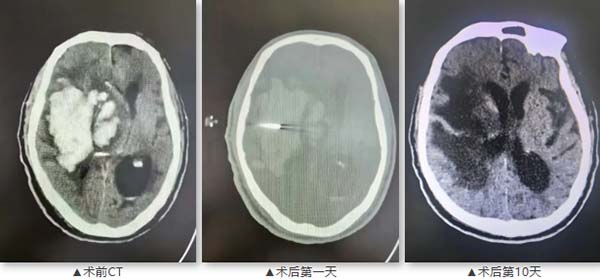

两名患者均为80岁以上高龄男性,分别因突发意识障碍入院。首例患者83岁,既往有高血压、多次脑梗死病史,长期口服阿司匹林,CT显示右侧基底节及丘脑大面积出血伴脑疝形成。第二例患者82岁,有20余年高血压、糖尿病史,曾行冠脉支架置入术,CT提示右侧额顶颞叶大面积脑出血。两名患者均病情危重,传统开颅手术风险极高。

第二例患者

首例患者于2025年9月15日接受手术,术后9天复查显示血肿基本清除;第二例患者于7月27日手术,术后10天血肿引流效果显著。两名患者术后病情均得到有效控制,生命得以挽救,稳定后转入社区医院进行康复治疗。患者家属对治疗效果表示满意,并赠送锦旗表达感谢。